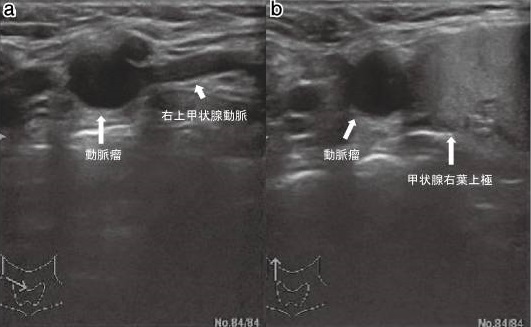

大動脈留だけではありません。動脈硬化による動脈瘤は、甲状腺を栄養する動脈にも起こります(日血外会誌 15:517-519,2006)。上甲状腺動脈瘤・下甲状腺動脈瘤は、これまでに40例未満の報告しかありません。大きさは0.8~6.2cmと様々で、大きさと破裂の有無とは関連しません。

甲状腺動脈瘤以外の末梢動脈瘤は、血栓塞栓症が多く、破裂は稀とされます。しかし、甲状腺動脈瘤で血栓塞栓症をおこした報告はありません。甲状腺動脈瘤の報告例で、破裂した割合は下甲状腺動脈瘤 58.3%、上甲状腺動脈瘤 25%で破裂瘤の20%は死亡しています。

甲状腺動脈瘤で破裂が多いメカニズムは不明です。 破裂前に見つけて無症候性(症状が無い)でもコイル塞栓術、あるいは外科的切除(甲状腺の同時部分切除も)を早急に行う必要があります(内分泌甲状腺外会誌 31(3):243-246,2014)。元々、甲状腺手術予定があるなら、同時切除もあり得ます。

甲状腺腫瘍を穿刺吸引細胞診する際、甲状腺動脈の外膜を傷付けて仮性動脈瘤を生じる事があります。動脈硬化した硬くて脆い所が動脈瘤に成り易いとされます。

破裂すると命にかかわるため、コイル塞栓術あるいは外科的切除(甲状腺の同時部分切除もあり)を早急に行う必要があります。[J Ultrasound Med. 2004 Dec;23(12):1675-8.]